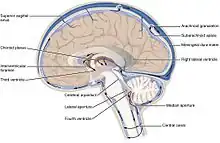

![]() Diagrama de las glándulas pituitaria y pineal, en el encéfalo humano (nomenclatura en inglés). | ||

La glándula pineal, también conocida como cuerpo pineal, conarium o epífisis cerebral, es una pequeña glándula endocrina que se encuentra en el cerebro de los vertebrados. Produce melatonina, una hormona derivada de la serotonina que afecta a la modulación de los patrones del sueño, tanto a los ritmos circadianos como estacionales. Su forma se asemeja a un pequeño cono de pino (de ahí su nombre), y está ubicada en el epitálamo cerca del centro del cerebro, entre los dos hemisferios, metida en un surco donde las dos mitades del tálamo se unen.

La glándula pineal es de color gris rojizo y del tamaño aproximado en los seres humanos de un grano de arroz (5-8 mm), se encuentra justo en el rostro dorsal al colículo superior, detrás y por debajo de la estría medular, entre los órganos del tálamo colocados lateralmente. Es parte del epitálamo. Se encuentra ubicada en la cisterna cuadrigémina y está bañada en el líquido cefalorraquídeo. Un pequeño receso pineal del tercer ventrículo se proyecta hacia el tallo de la glándula. La glándula pineal es una estructura de línea media en forma de cono de pino.